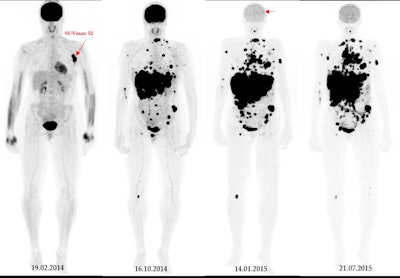

A 49-year-old patient with primary clinical stage III melanoma underwent F-18 FDG-PET. The primary tumor Breslow thickness was 6.5 mm. On initial F-18 FDG-PET images, this patient had a high SUVmax (52), resulting in limited survival with the occurrence of brain metastasis in the first year of follow-up (horizontal arrow). Notably, during the course of the treatment, the patient underwent surgical removal of the primary tumor as well as lymph node dissection, followed by neoadjuvant radiotherapy and immunotherapy. Image courtesy of Cancers.

All patients underwent F-18 FDG-PET/CT for initial staging, as well as serial imaging follow-ups for diagnosing brain metastasis. The researchers culled baseline parameters from the PET/CT imaging and correlated the parameters with the occurrence of brain metastases using risk regression models. The median follow-up was six years.

According to the findings, baseline peak standardized uptake values (pSULpeak) – a parameter representing the highest FDG radiotracer activity in target tumors – were associated with earlier brain tumors.

For example, if a patient had a high pSULpeak value of 19, then the risk of brain metastasis development was 80% after approximately 53 months, and with a pSULpeak value of 26, the patient had an 80% risk after about 39 months, they wrote.

“As the baseline pSULpeak increased, the likelihood of the patient developing brain metastases rose and occurred at an earlier time,” the group wrote.